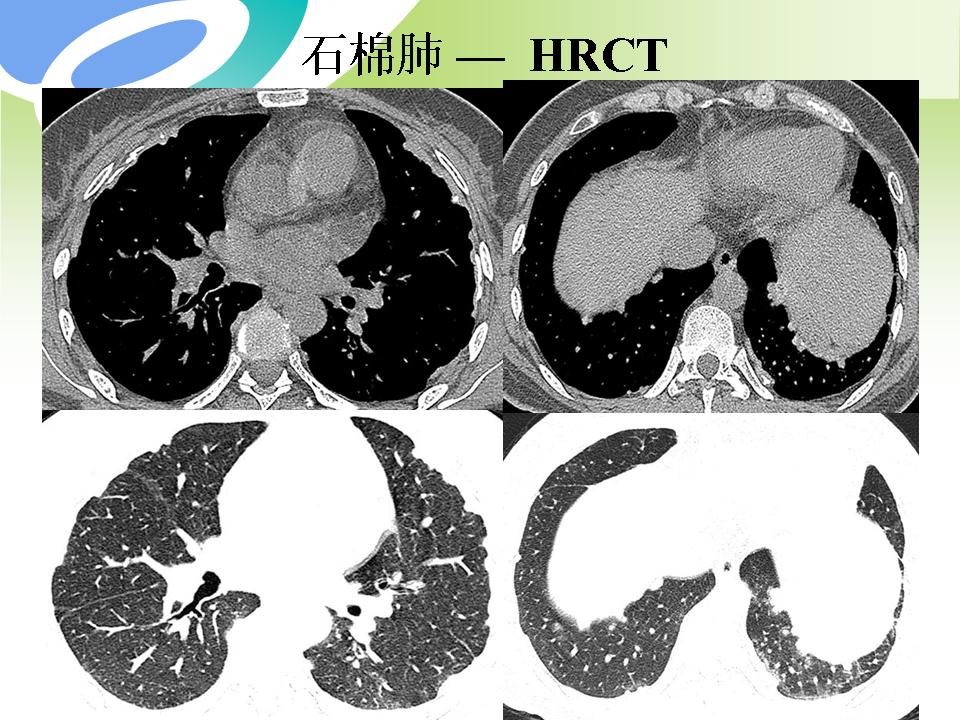

肺部病变的CT基本征象